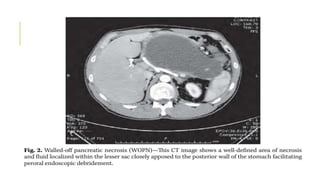

WALLED-OFF PANCREATIC NECROSIS (WOPN)

- It is a PFC that contains solid necrotic debris that contains a well defined

capsule with or without fluid component

- Usually develops after necrotising pancreatitis

- Small percentage may resolve spontaneously

- Majority require Surgical Intervention